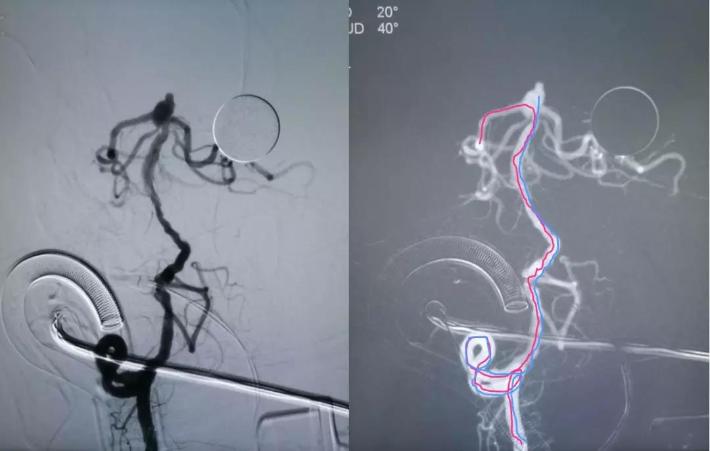

预置入支架导管,栓塞动脉瘤用微导管头端超选进入动脉瘤腔,通过支架导管送入Enterprise支架(4.5*22mm)并打开支架,填入弹簧圈栓塞夹层动脉瘤。但此时发现大脑前动脉A1段不显影。

治疗后

对侧造影评估,前交通开放,左侧大脑前动脉经开放良好的前交通动脉向右侧大脑前动脉A2段各分支血管供血良好,结束手术

✔Enterprise支架释放后,右侧大脑前动脉A1段未显影,考虑可能为支架打开后,对病变段血管的修复及一定血流导向作用,大脑中动脉前向血流增加,而原本纤细的左侧大脑前动脉A1段血流减少,对侧大脑前动脉通过前交通动脉向左侧大脑前动脉A2段主流供血,由于血流对冲作用至左侧大脑前动脉A1段不显影。后对侧评估前交通开放,对侧代偿良好,结束手术。术后患者亦未再出现新的神经系统体征,肢体活动及语言功能恢复良好,1周后头颅CT未见新发梗死灶。